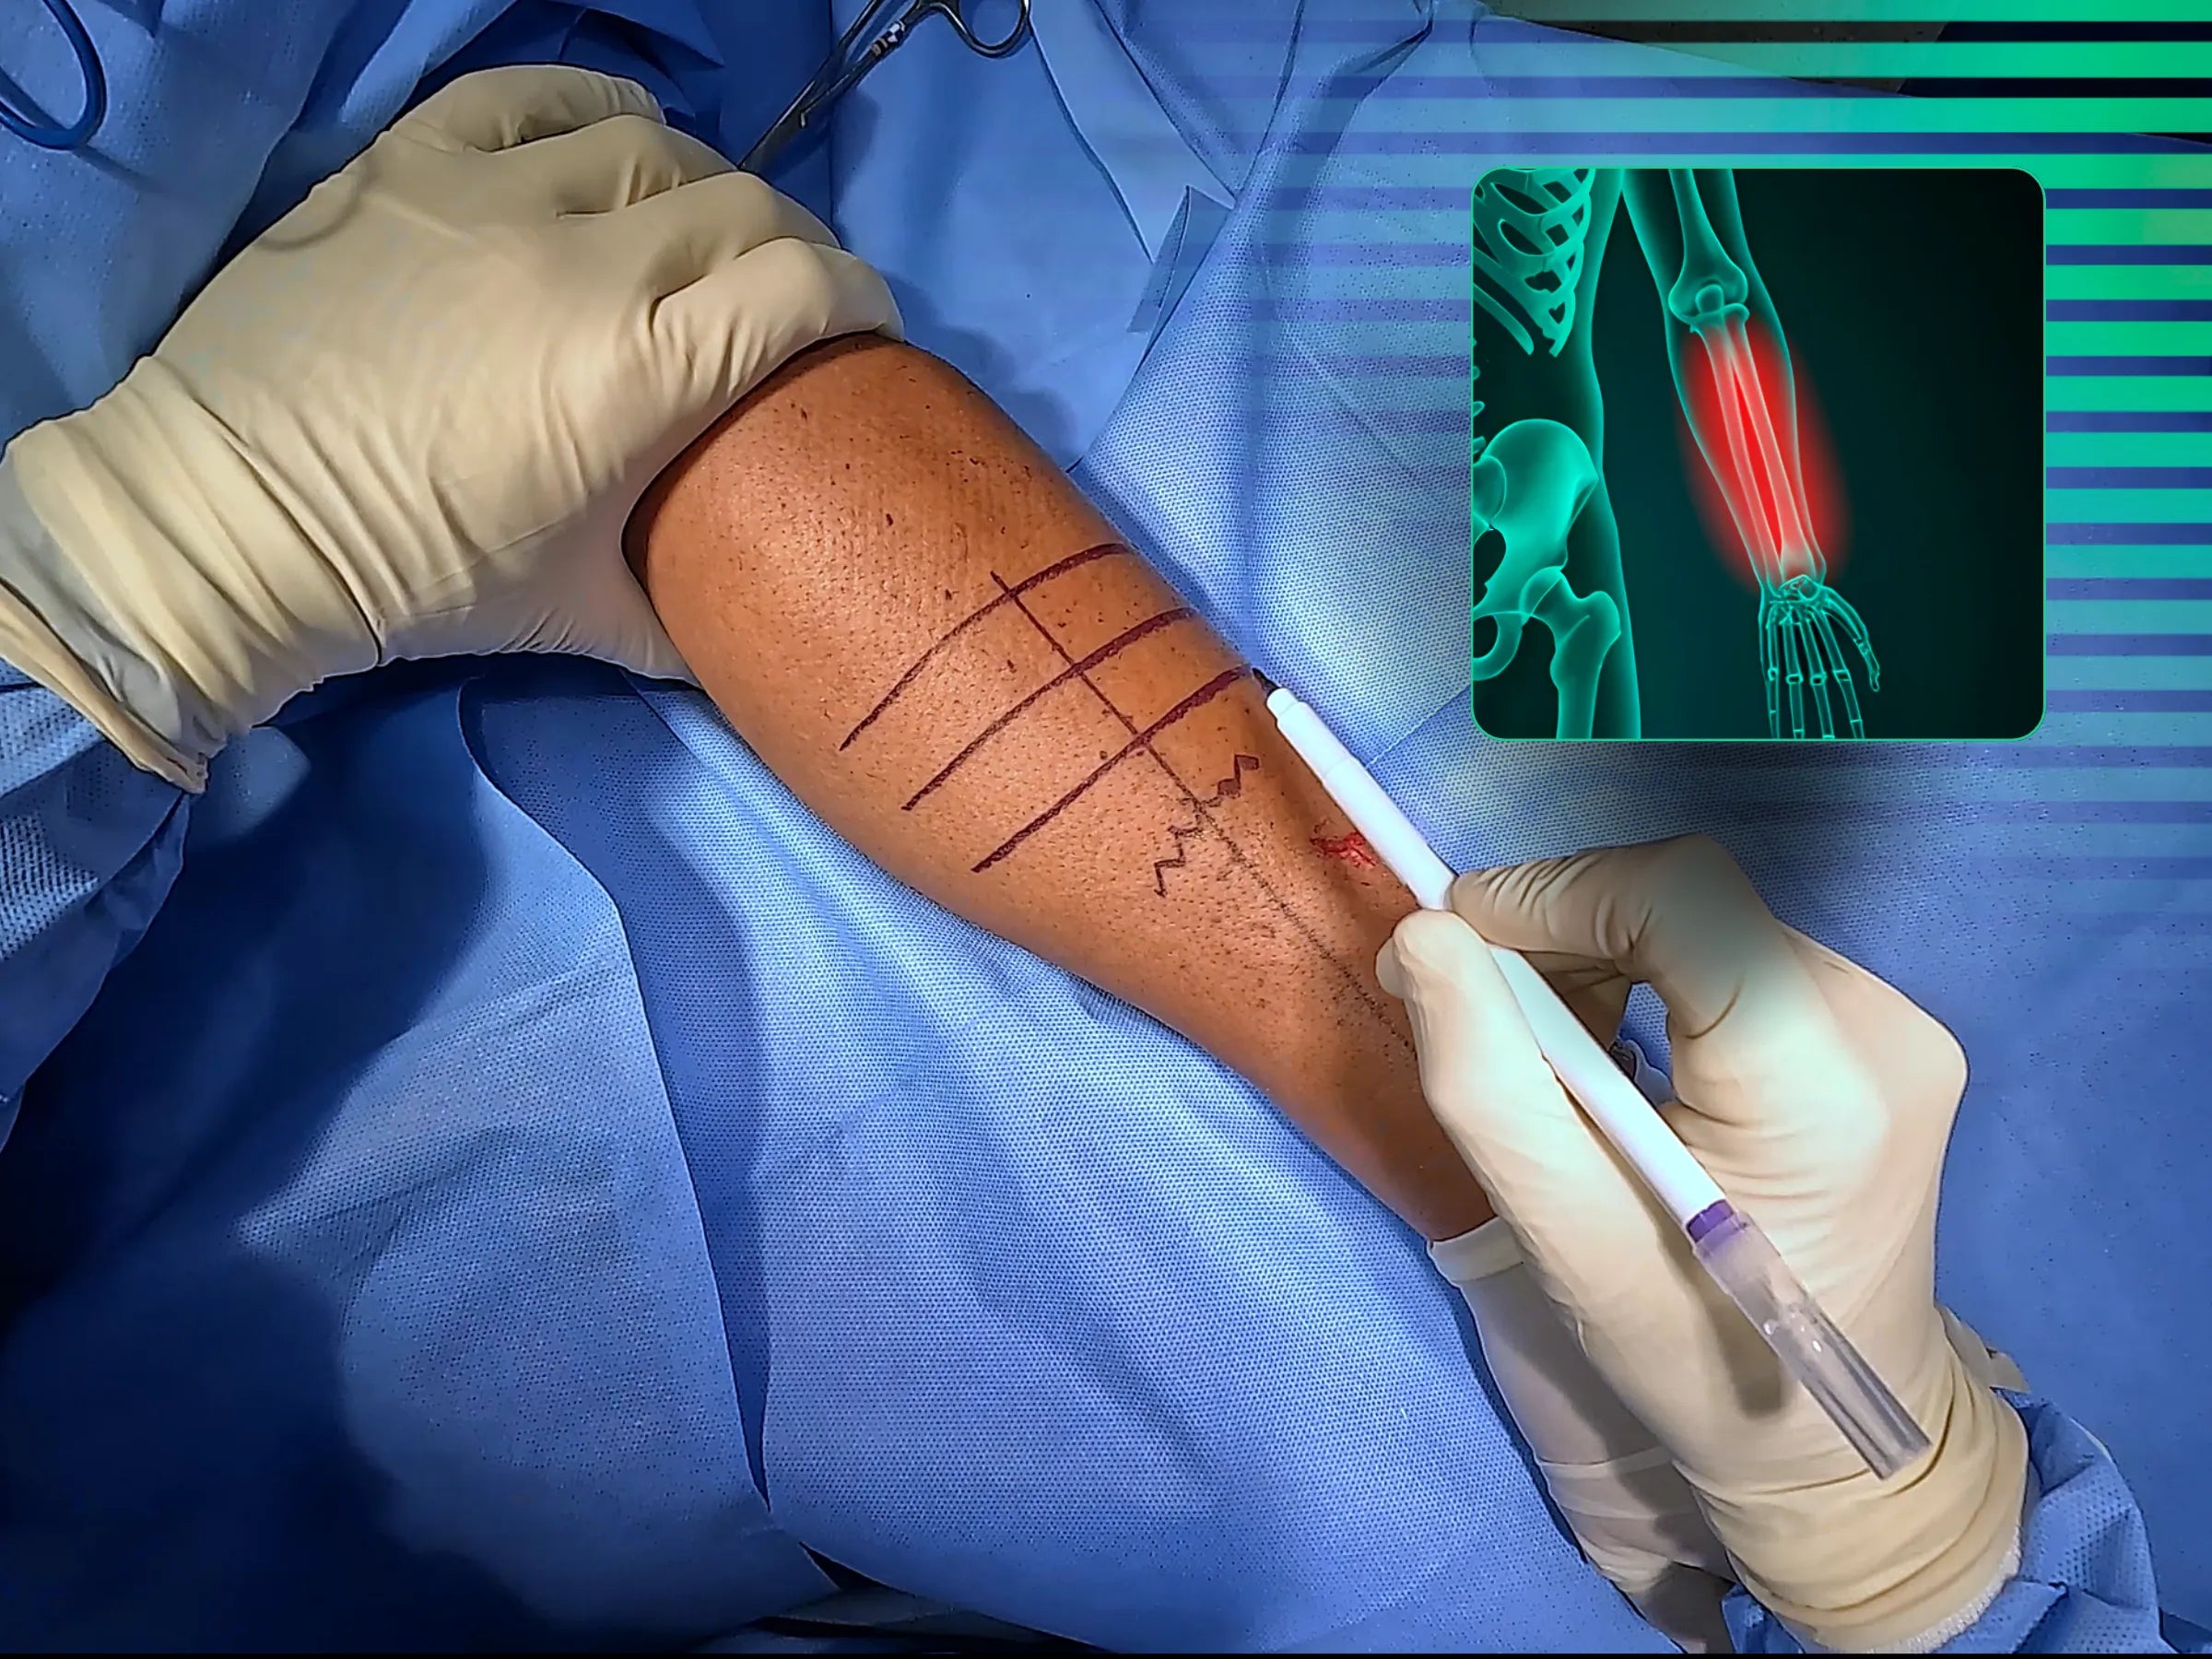

- Planejamento e Marcação: Aprenda a marcar e palpar o tubérculo de Lister e o epicôndilo lateral, traçando uma linha entre eles. Utilize a palpação muscular para definir o local exato da incisão cutânea e o intensificador de imagem para localizar o sítio da fratura.

- Incisão e Dissecção: Domine a incisão cutânea com eletrocauterização e hemostasia. Aprofunde a dissecção para identificar os intervalos musculares, utilizando gaze para dissecção romba e visualizando a fáscia para o plano ideal de acesso, preservando os planos naturais do antebraço.